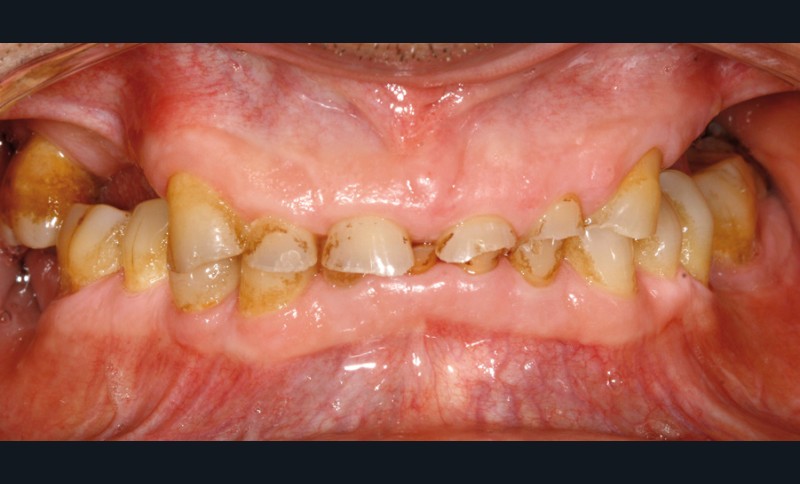

Un patient de 68 ans arrive au cabinet ; il présente de nombreux édentements ainsi qu’une usure parafonctionnelle très avancée.

Il consulte en urgence pour une douleur sur la 23 dont le traitement endodontique s’impose. Il relate également des difficultés croissantes pour s’alimenter.

• L’examen intrabuccal montre de nombreux édentements non compensés (14, 15, 16, 24, 25, 26, 27, 47 et 36) ainsi que des pertes de substance très importantes, notamment dans le secteur antérieur.

Une attrition sévère, couplée à une occlusion sans calage postérieur, a engendré des difficultés pour s’alimenter.

La perte de dimension verticale par usure prématurée nécessite d’augmenter cette dernière de façon importante, et en une seule fois.

• Le bilan esthétique nous indique plusieurs points disgracieux :

– dysharmonie des contours gingivaux (ligne des collets) avec une ligne du sourire basse [1] ;

– perte de substance extrême du bloc incisivo-canin maxillaire et des incisives mandibulaires ;

– visibilité très limitée des dents lors d’un sourire forcé ;

– égressions compensatoires.